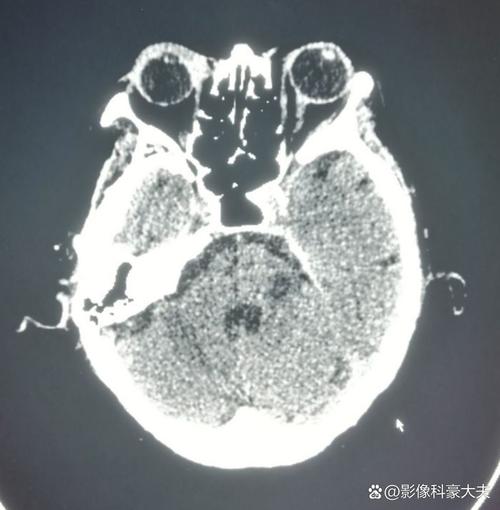

这是一个非常重要且紧急的医疗问题,脑梗导致脸麻,最常见和最典型的梗塞位置是大脑半球的特定区域,尤其是大脑中动脉的供血区域。

负责控制对侧脸部感觉和运动的神经中枢出现了缺血性坏死。

最关键的供血血管:大脑中动脉

上述提到的这些关键区域(大脑皮层的感觉和运动中枢、内囊)主要由大脑中动脉及其分支来供血。

大脑中动脉闭塞或狭窄是导致脑梗脸麻的最常见原因,大脑中动脉是大脑半球最主要的供血血管,梗塞后影响的范围广,症状也通常比较典型和严重。